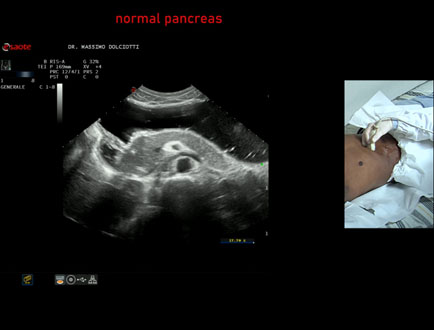

Data inserimento: 11/04/2025

Ecografia del: 26/03/2025

Strumento: Esaote MyLab Eight

Sonda: Convex Multifrequenza 1-8 MHz

Età Paziente: F 43 anni

Motivazione dell'esame: alvo alterno e pollachiuria.

Commento all'esame: le immagini ed il video documentano il pancreas, con regione cefalica, corpo e coda, ad ecostruttura e morfovolumetria regolare, di normale aspetto ipoecogeno.

Conclusioni: pancreas normale (normal pancreas).

Presentazione: Dr. Massimo Dolciotti - Ancona

Elaborazione digitale: Andrea Dini - Ancona